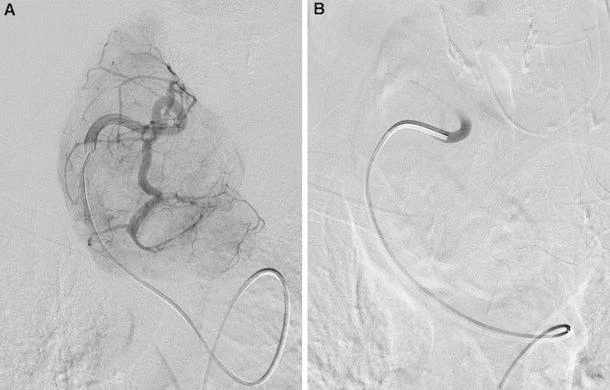

Thyroid Artery Embolization is a treatment that does not require a surgery. It works by slowing down the blood flow to parts of the thyroid tissue. This is done by blocking thyroid artery branches with tiny particles that are put in place using a small tube called a catheter. The goal of Thyroid Artery Embolization is to reduce the blood supply to the treated area. This can help the targeted thyroid tissue get smaller or become less active over time depending on what’s wrong, with the thyroid tissue.

This procedure is really different from thyroid surgery. You do not get a cut in your neck and the thyroid gland is not taken out. What happens is that a small hole is made, in the groin area or sometimes the wrist and a thin tube is put through the blood vessels. The doctor uses imaging to guide the tube to the arteries that go to the thyroid. Then the doctor puts material into the arteries to stop the blood flow to the parts of the thyroid that are causing problems. The doctor is very careful to stop the blood flow to the bad areas and not to the healthy tissues, around them. The thyroid procedure is done to help the thyroid gland. The doctor uses the special material to help fix the thyroid.

To understand thyroid artery embolization think about this: thyroid tissue needs blood to grow and work properly. The thyroid gland has a lot of blood vessels. Some thyroid problems can even have blood vessels in certain areas. Thyroid artery embolization is a way to slow down the blood flow, to the thyroid tissue that is causing problems. It does this in a careful and controlled way. Thyroid artery embolization helps by reducing blood flow to the targeted thyroid tissue.

During the treatment the doctor uses pictures to help guide a tube to the thyroid arteries.

The doctor finds the branches that bring blood to the bad part of the thyroid gland the part that is causing problems or is abnormal.

Then the doctor puts in tiny particles these particles are called embolic particles to slow down the blood flow, to the bad part of the thyroid gland to the abnormal tissue of the thyroid gland.

Following embolization, the body begins a gradual healing response. Over time, the treated tissue may reduce in size and the sense of neck pressure or compression can improve. If the treated portion was contributing to overactivity, symptoms may improve as function in that segment reduces. Because the effect develops gradually, improvements are typically measured over weeks to months, often with follow-up imaging and thyroid function testing.